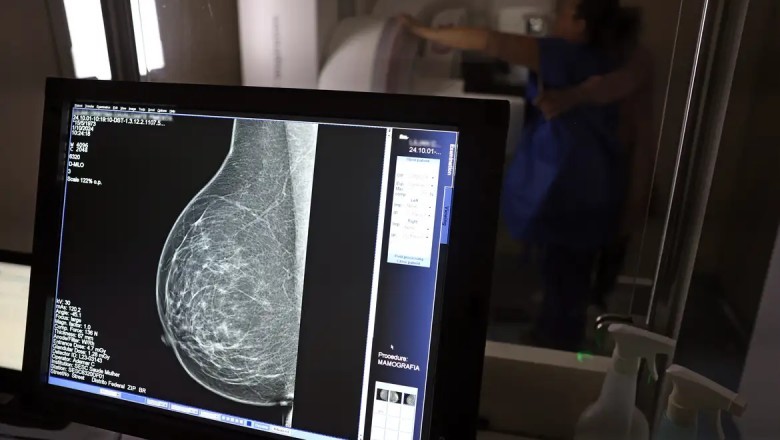

Segundo o CBR, os dados reforçam a necessidade de ampliar o rastreamento da doença por meio da mamografia também para mulheres com menos de 50 anos e acima dos 70 anos. Atualmente, a recomendação do Sistema Único de Saúde (SUS) contempla apenas mulheres entre 50 e 69 anos.

Entre janeiro de 2018 e dezembro de 2023, o país registrou 319.378 diagnósticos de câncer de mama. Do total, 157.439 ocorreram na faixa etária atualmente recomendada para rastreamento (50 a 69 anos). Já entre mulheres de 40 a 49 anos, foram contabilizados 71.204 casos. Outras 19.576 mulheres, com idade entre 35 e 39 anos, também receberam o diagnóstico, totalizando 33% dos casos fora do público prioritário.

Na população acima dos 70 anos, foram identificados 53.240 diagnósticos no período.

O levantamento mostra ainda um aumento de 59% no total de diagnósticos da doença em seis anos. Em 2018, foram registrados 40.953 casos; em 2023, o número subiu para 65.283.